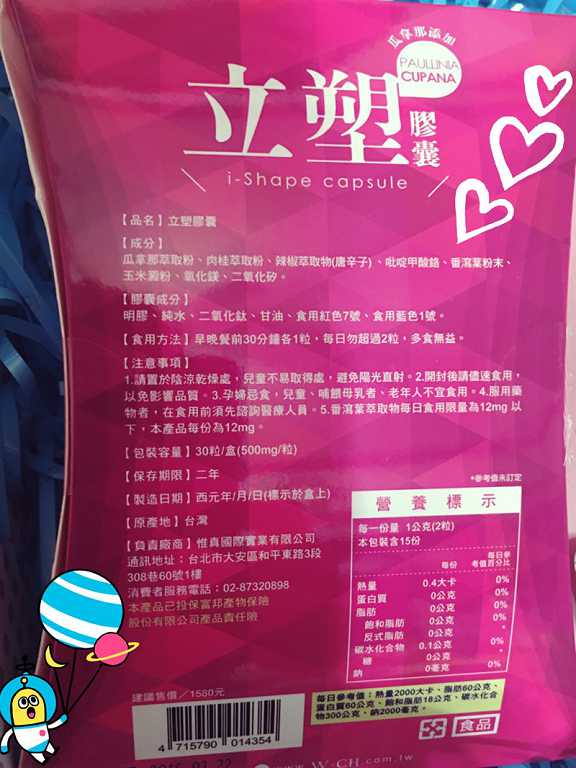

Supercut塑魔纖立塑膠囊的成分有:瓜拿那萃取粉、肉桂萃取粉、辣椒萃取物(唐辛子)、吡啶甲酸鉻、番瀉葉粉末、玉米澱粉、氧化鎂、二氧化矽。

食用方式:早晚餐前30分鐘各1粒,每日不超過2粒。(多食無益)

番瀉葉萃取物每日食用限量為12mg以下,